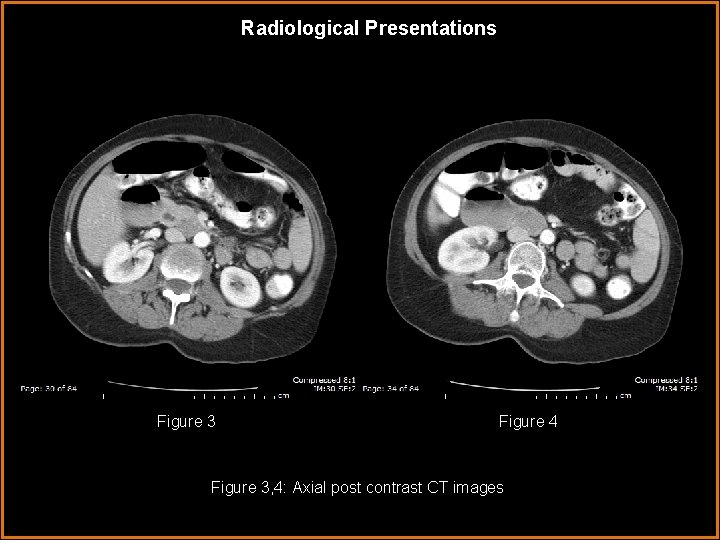

Radiological Presentations Figure 3 Figure 4 Figure 3, 4: Axial post contrast CT images

Findings and Differentials Findings: CT: There is dilatation of the 1 st-3 rd portions of the duodenum up to 5 cm with a transition point where the duodenum crosses between the aorta and superior mesenteric artery. The aortomesenteric distance as measured on the axial images where the duodenum crosses the aorta is approximately 7. 3 mm (figure 15) and the aortomesenteric angle as measured on the sagittal images measures approximated 15 o (figure 16). A hiatus hernia was present on images not presented.

Discussion As previously mentioned, the aortomesenteric angle and distance are decreased in patients with SMA syndrome. Patients with SMA syndrome have aortomesenteric distances of 2 -8 mm whereas the normal range is 10 -28 mm. Similarly, patients with SMA syndrome have decreased aortomesenteric angles of 6 -22 o whereas the normal range is 25 -60 o. 3 -7 These measurements have traditionally been obtained with angiography, but today they are more commonly obtained with CT. CT is noninvasive and is more effective at evaluating for other causes of duodenal dilation than conventional angiography. Also, if the SMA is anterolateral rather than directly anterior to the aorta, lateral projection angiography may underestimate the true aortomesenteric distance. 6 -7 In the presented case, many of the radiographic and clinical features of SMA syndrome are present. The patient presented with symptoms of high intestinal obstruction including bilious vomiting. On CT the duodenum was dilated with a transition point at the 3 rd portion and both the aortomesenteric distance and aortomesenteric angle were decreased measuring 7. 3 mm and 15 o respectively. On upper GI there was also a dilated duodenum with the suggestion of an abrupt vertical cutoff of contrast at the 3 rd portion just to the right of the spine.